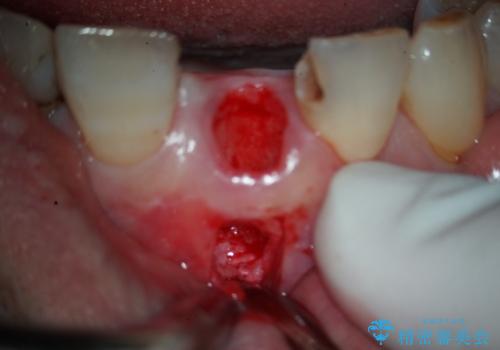

治療は、まず感染の原因となっていた前歯を慎重に抜歯し、抜歯と同時にインプラントを埋入しました。審美性を重視する部位であるため、骨や歯ぐきのボリュームを維持するための補填処置も併用しています。術後は仮歯を装着し、見た目を保ちながらインプラントと骨がしっかりと結合するのを待ちました。